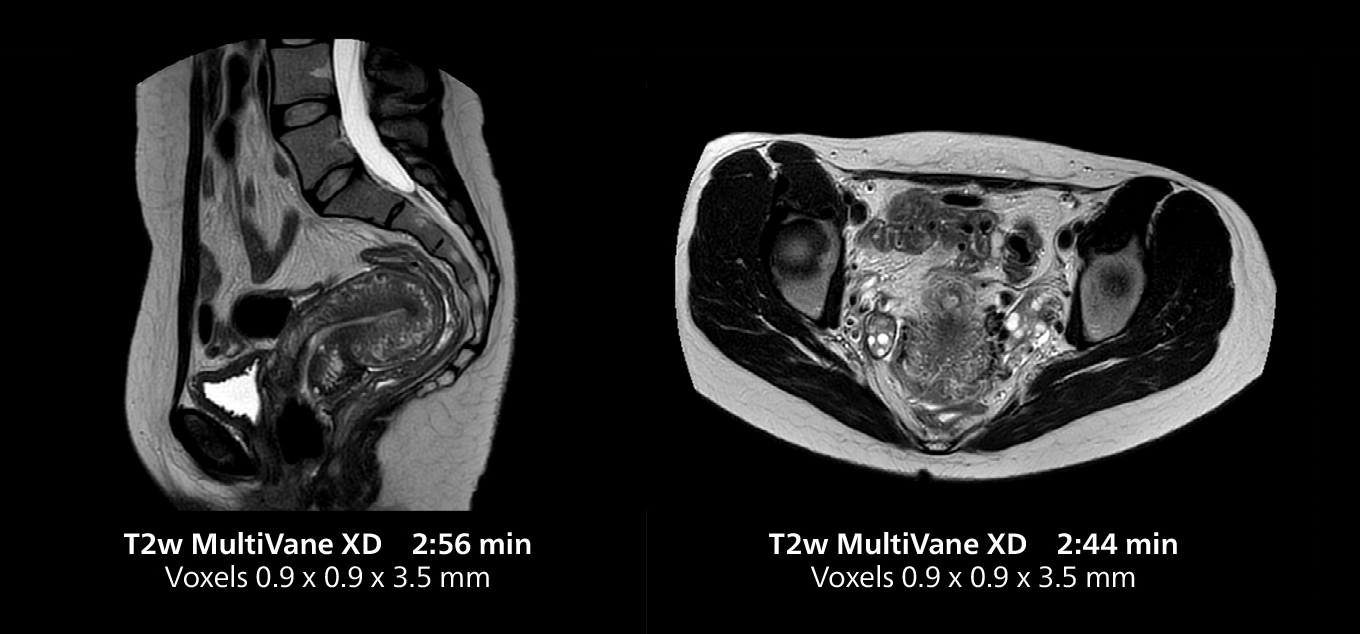

Female pelvis imaging

This MRI case illustrates good resolution and imaging quality obtained within reasonable scan times using the MR 5300 1.5T system with the anterior torso cardiac coil that allows use of a large field of view (FOV).